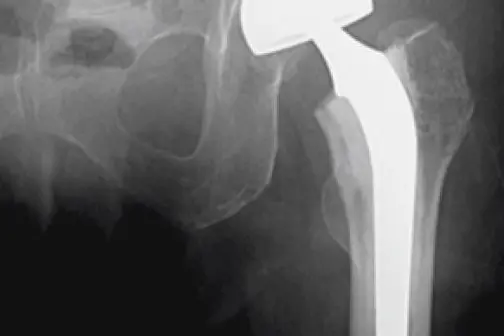

Ved hoftebrot skil ein mellom brot nedanfor lårhalsen og lårhalsbrot. Dei fleste tilfella av lårhalsbrot må opererast med ei protese. Kirurgen vil då erstatte hoftekula med ei kunstig hoftekule. I nokre tilfelle er det mogleg å operere ved bruk av to skruar.

Lårhalsbrot behandla med protese.